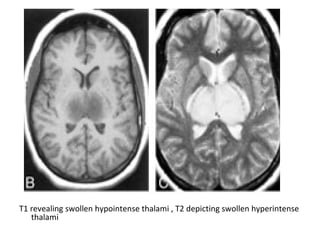

T1 revealing swollen hypointense thalami , T2 depicting swollen hyperintense

thalami